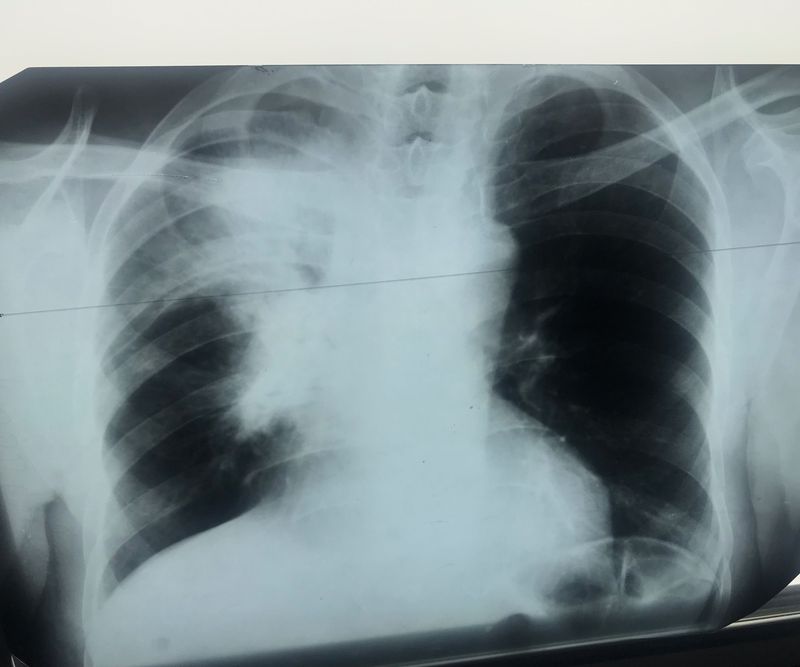

X- ray description

Please help with the diagnosis doctors

Xray